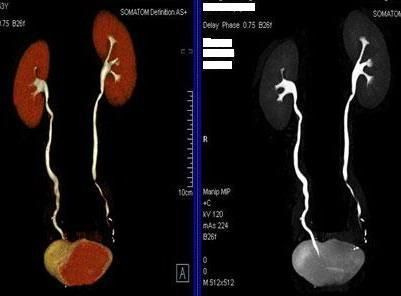

二、多層螺旋CT頭頸部及體部血管成像技術:

該機掃描覆蓋範圍廣、時間短,多種後處理分析軟件能顯示各血管細小分支,可以清晰顯示動脈瘤、動脈夾層、血管畸形、血管狹窄及動脈粥樣硬化斑塊等,适用于頭頸部血管成像、肺動脈成像、胸腹部血管成像及四肢血管成像。

4、腎動脈血管成像(腎動脈狹窄):

5、下肢動脈血管成像:

全尿路成像(CTU):